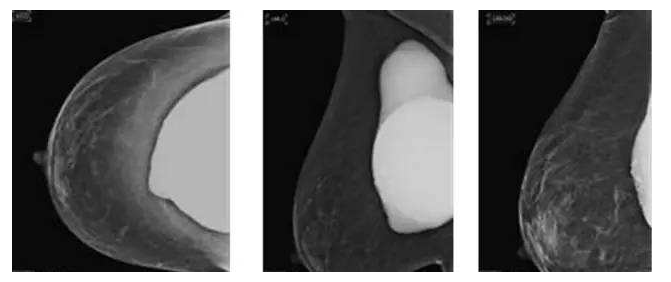

假体隆胸10年后将面临什么样的问题?

假体隆胸手术发展至今已有几十年历程,随之时代的发展,医学的进步,现代隆胸技术在不断升级,假体质量也在不断提高。现代信息的广泛传播,也让受众对于隆胸手术的了解全面化。一台成功的隆胸手术可以维持10年的时间,那么为什么是10年成为了隆胸的关键时期?10年后隆胸的人会面临怎样的问题?

因为假体质量不同、医生操作方式不同、个人体质存在差异,所以具体的存放时间无法被预估。所以假体隆胸10年后,应每年进行B超、核磁共振检查,以确保假体的完整性和安全性,排除并发症,如遇问题,可尽早进行处理。

假体老化最常出现的现象,比如囊壁钙化,渗漏,甚至破裂,还会随着人体组织的老化出现下垂问题。

囊壁钙化:硅胶假体在胸部存放时间过长,在硅胶和自身组织包膜之间,就有可能形成钙化沉淀。轻微的钙化不会对人体造成伤害,无需在意。但如果钙化出现较大的结块,而且集中出现在假体周围,便需要做组织取出或手术。

假体渗漏、破裂:囊膜皱褶经反复运动而老化破裂,后期渗漏或破裂,有纤维囊挛缩或急性炎症现象。假体破裂的发生率虽然很低,当假体出现明显的手感变化,形态的变化,那么这个时候就可能出现了假体的破裂,如果出现假体破裂就需要置换假体。

假体松弛下垂

如果出现假体隆胸变软下垂的问题可能是假体置入层次的问题,假体如果是放在胸部腺体下,它会随着自体的胸部往下垂而一起下垂,如果假体放在胸大肌下,那么就会出现腺体往下走,而假体不往下走,就有可能形成四个胸部的情况。

最后提醒大家,一般情况下假体维持10-20年基本没有问题,不必对此过于忧虑。时常观察胸部大小变化,手感软硬程度,每年做好定期检查即可。